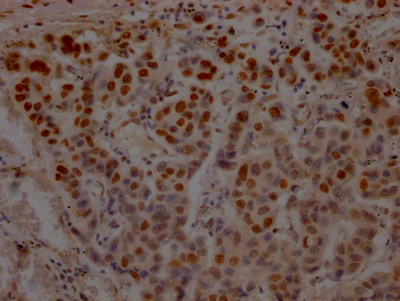

IHC image of CSB-RA214807A0HU diluted at 1:100 and staining in paraffin-embedded human breast cancer performed on a Leica BondTM system. After dewaxing and hydration, antigen retrieval was mediated by high pressure in a citrate buffer (pH 6.0). Section was blocked with 10% normal goat serum 30min at RT. Then primary antibody (1% BSA) was incubated at 4℃ overnight. The primary is detected by a Goat anti-rabbit IgG polymer labeled by HRP and visualized using 0.05% DAB.

產(chǎn)品描述:CSB-RA214807A0HU TP53重組單克隆抗體是針對腫瘤抑制蛋白p53研發(fā)的高特異性檢測試劑。該抗體通過重組技術(shù)制備,靶向人源TP53基因編碼的p53蛋白,該蛋白作為關(guān)鍵的細(xì)胞周期調(diào)控因子,在DNA損傷修復(fù)、細(xì)胞凋亡及腫瘤發(fā)生中發(fā)揮核心作用。經(jīng)嚴(yán)格驗(yàn)證,本產(chǎn)品在ELISA實(shí)驗(yàn)中表現(xiàn)出優(yōu)異的抗原結(jié)合能力,同時(shí)在免疫組化(IHC)應(yīng)用中可清晰顯示組織樣本中p53蛋白的定位表達(dá),推薦使用稀釋比為1:50-1:200時(shí)能獲得理想染色效果,適用于石蠟包埋組織切片分析。其高親和力與低交叉反應(yīng)性特點(diǎn),使其成為研究腫瘤發(fā)生機(jī)制、細(xì)胞應(yīng)激反應(yīng)通路及基因功能調(diào)控的可靠工具,尤其適用于癌癥相關(guān)基礎(chǔ)研究中的蛋白表達(dá)模式分析、病理模型構(gòu)建及分子互作實(shí)驗(yàn)。本抗體采用單克隆重組技術(shù)生產(chǎn),具有批次間高度一致性,可在-20℃長期穩(wěn)定保存,建議分裝后避免反復(fù)凍融以維持最佳活性,為科研工作者提供穩(wěn)定高效的檢測支持。

Application Recommended Dilution IHC 1:50-1:200 -